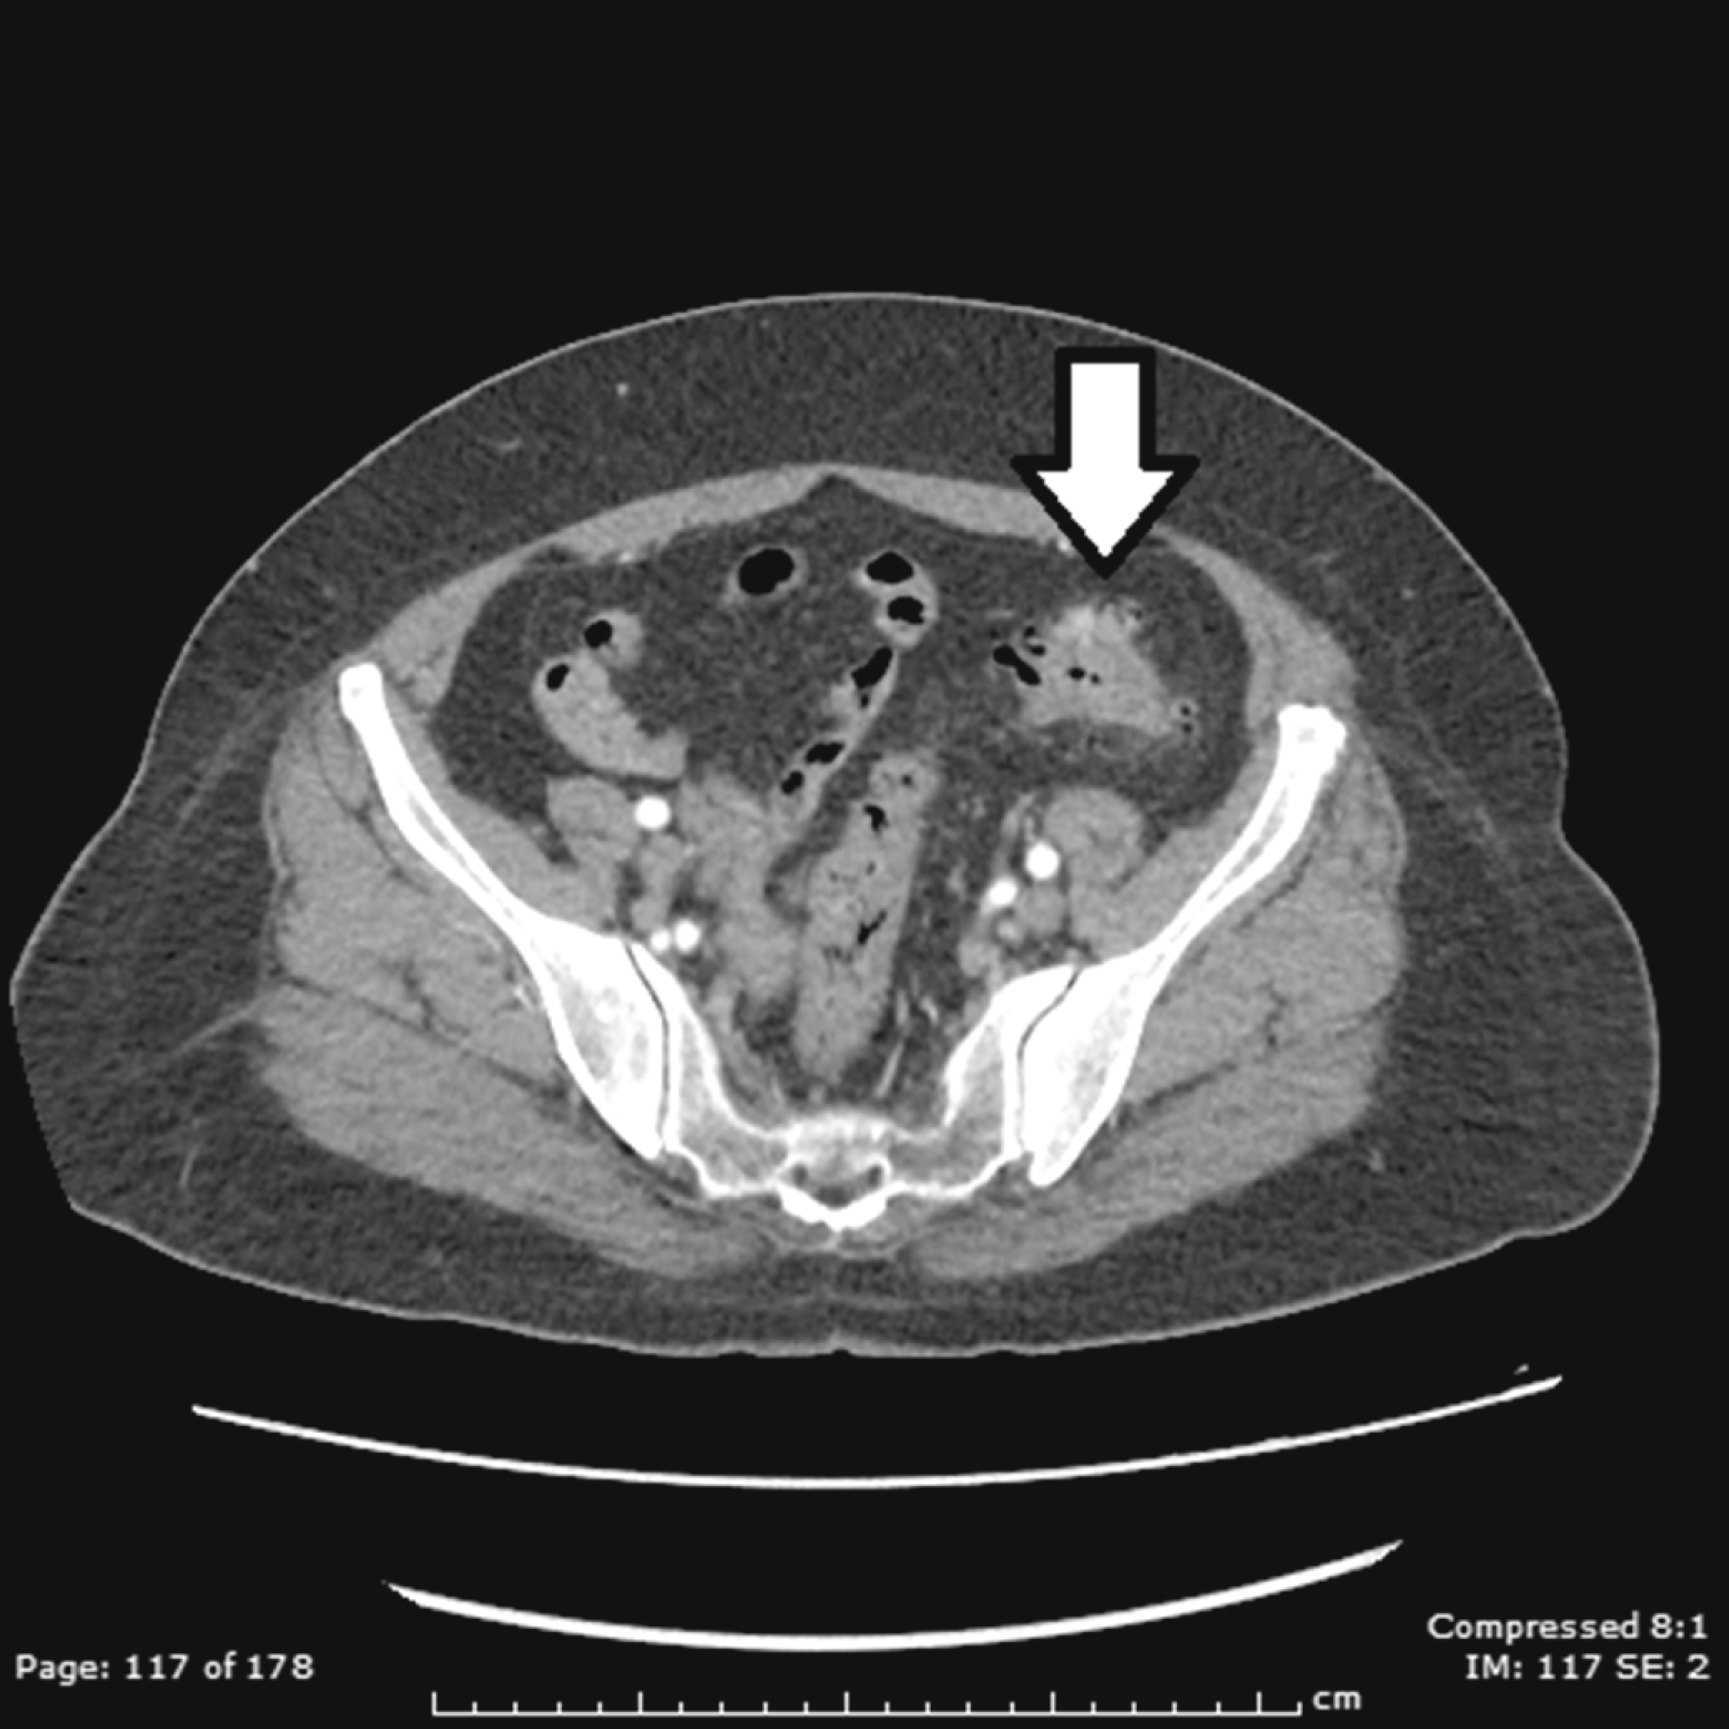

Abdominal CT has become the standard of care for diagnosing diverticulitis. A CT without contrast can identify the presence of diverticular disease. CT with intravenous (IV) contrast is commonly used to assess for diverticulitis. However, CT with both IV and enteric (either oral or rectal) contrast is the ideal method to assess for diverticulitis and any associated complications, with 98% sensitivity and 99% specificity. CT findings may include colonic wall thickening, pericolonic fat stranding, localized perforation (also known as micro-perforation), abscesses, as well as free air or fluid ( Figs. 81.1–81.3 ). While generally outside the scope of ED practice, the Hinchey staging system can be used to stratify diverticulitis based on the level of abscess formation or perforation ( Box 81.4 ).

Uncomplicated diverticulitis (arrow) showing multiple air-filled structures lining the edge of the left colon (diverticuli), and hazy outer border of bowel segment (fat stranding) indicative of inflammation.

Computed Tomography Imaging Demonstrating Diverticulitis With Abscess Formation.

From Sartelli M, Moore FA, et al. A proposal for a CT driven classification of left colon acute diverticulitis. World J. Emerg. Surg . 2015;10(3):1–11, Fig. 4.